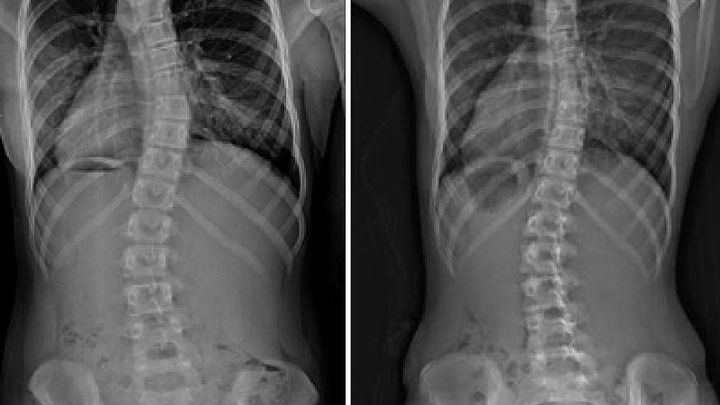

At 11years old, he has been diagnosed with a rare form of scoliosis.

His doctors have determined he will need to be immediately fitted for a brace that he will need to wear for 22 hours per day, (as an initial attempt to help correct his condition) with the possibility of additional treatment or surgery, due to the positioning of the syrinx in his spine and location of the curve.

Stock photos used for privacy reasons-